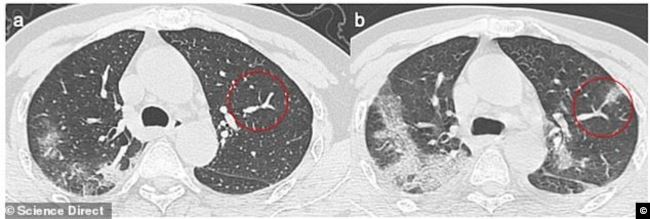

نشرت صحيفة" ديلي ميل" البريطانية مجموعة صور وصفتها بالمروعة لتدمير فيروس كورونا المستجد، رئات شخصين في الستينات من العمر من مدينة ووهان الصينية، كانا في رحلة إلى إيطاليا.

وقام باحثون في المعهد الوطني للأمراض المعدية في روما بدراسة الشخصين بعد اختبار إيجابي للفيروس في 29 يناير 2020.

وكان المريضان (الأول يبلغ من العمر 67 عاما، والثانية 65 عاما)، يتمتعان بصحة جيدة، لكن المريضة الثانية كانت تتناول أدوية لضغط الدم المرتفع.

وكشفت صور الأشعة السينية وصور الأشعة المقطعية كيف دمر الفيروس  وجهازهما التنفسي بطريقة مماثلة  لتأثير فيروسي سارس وميرس وقد أظهرت الأشعة المقطعية للمريضين تورم الأنسجة الرخوة في الرئة، وقد امتلأت بالصديد والدم، أو الماء.